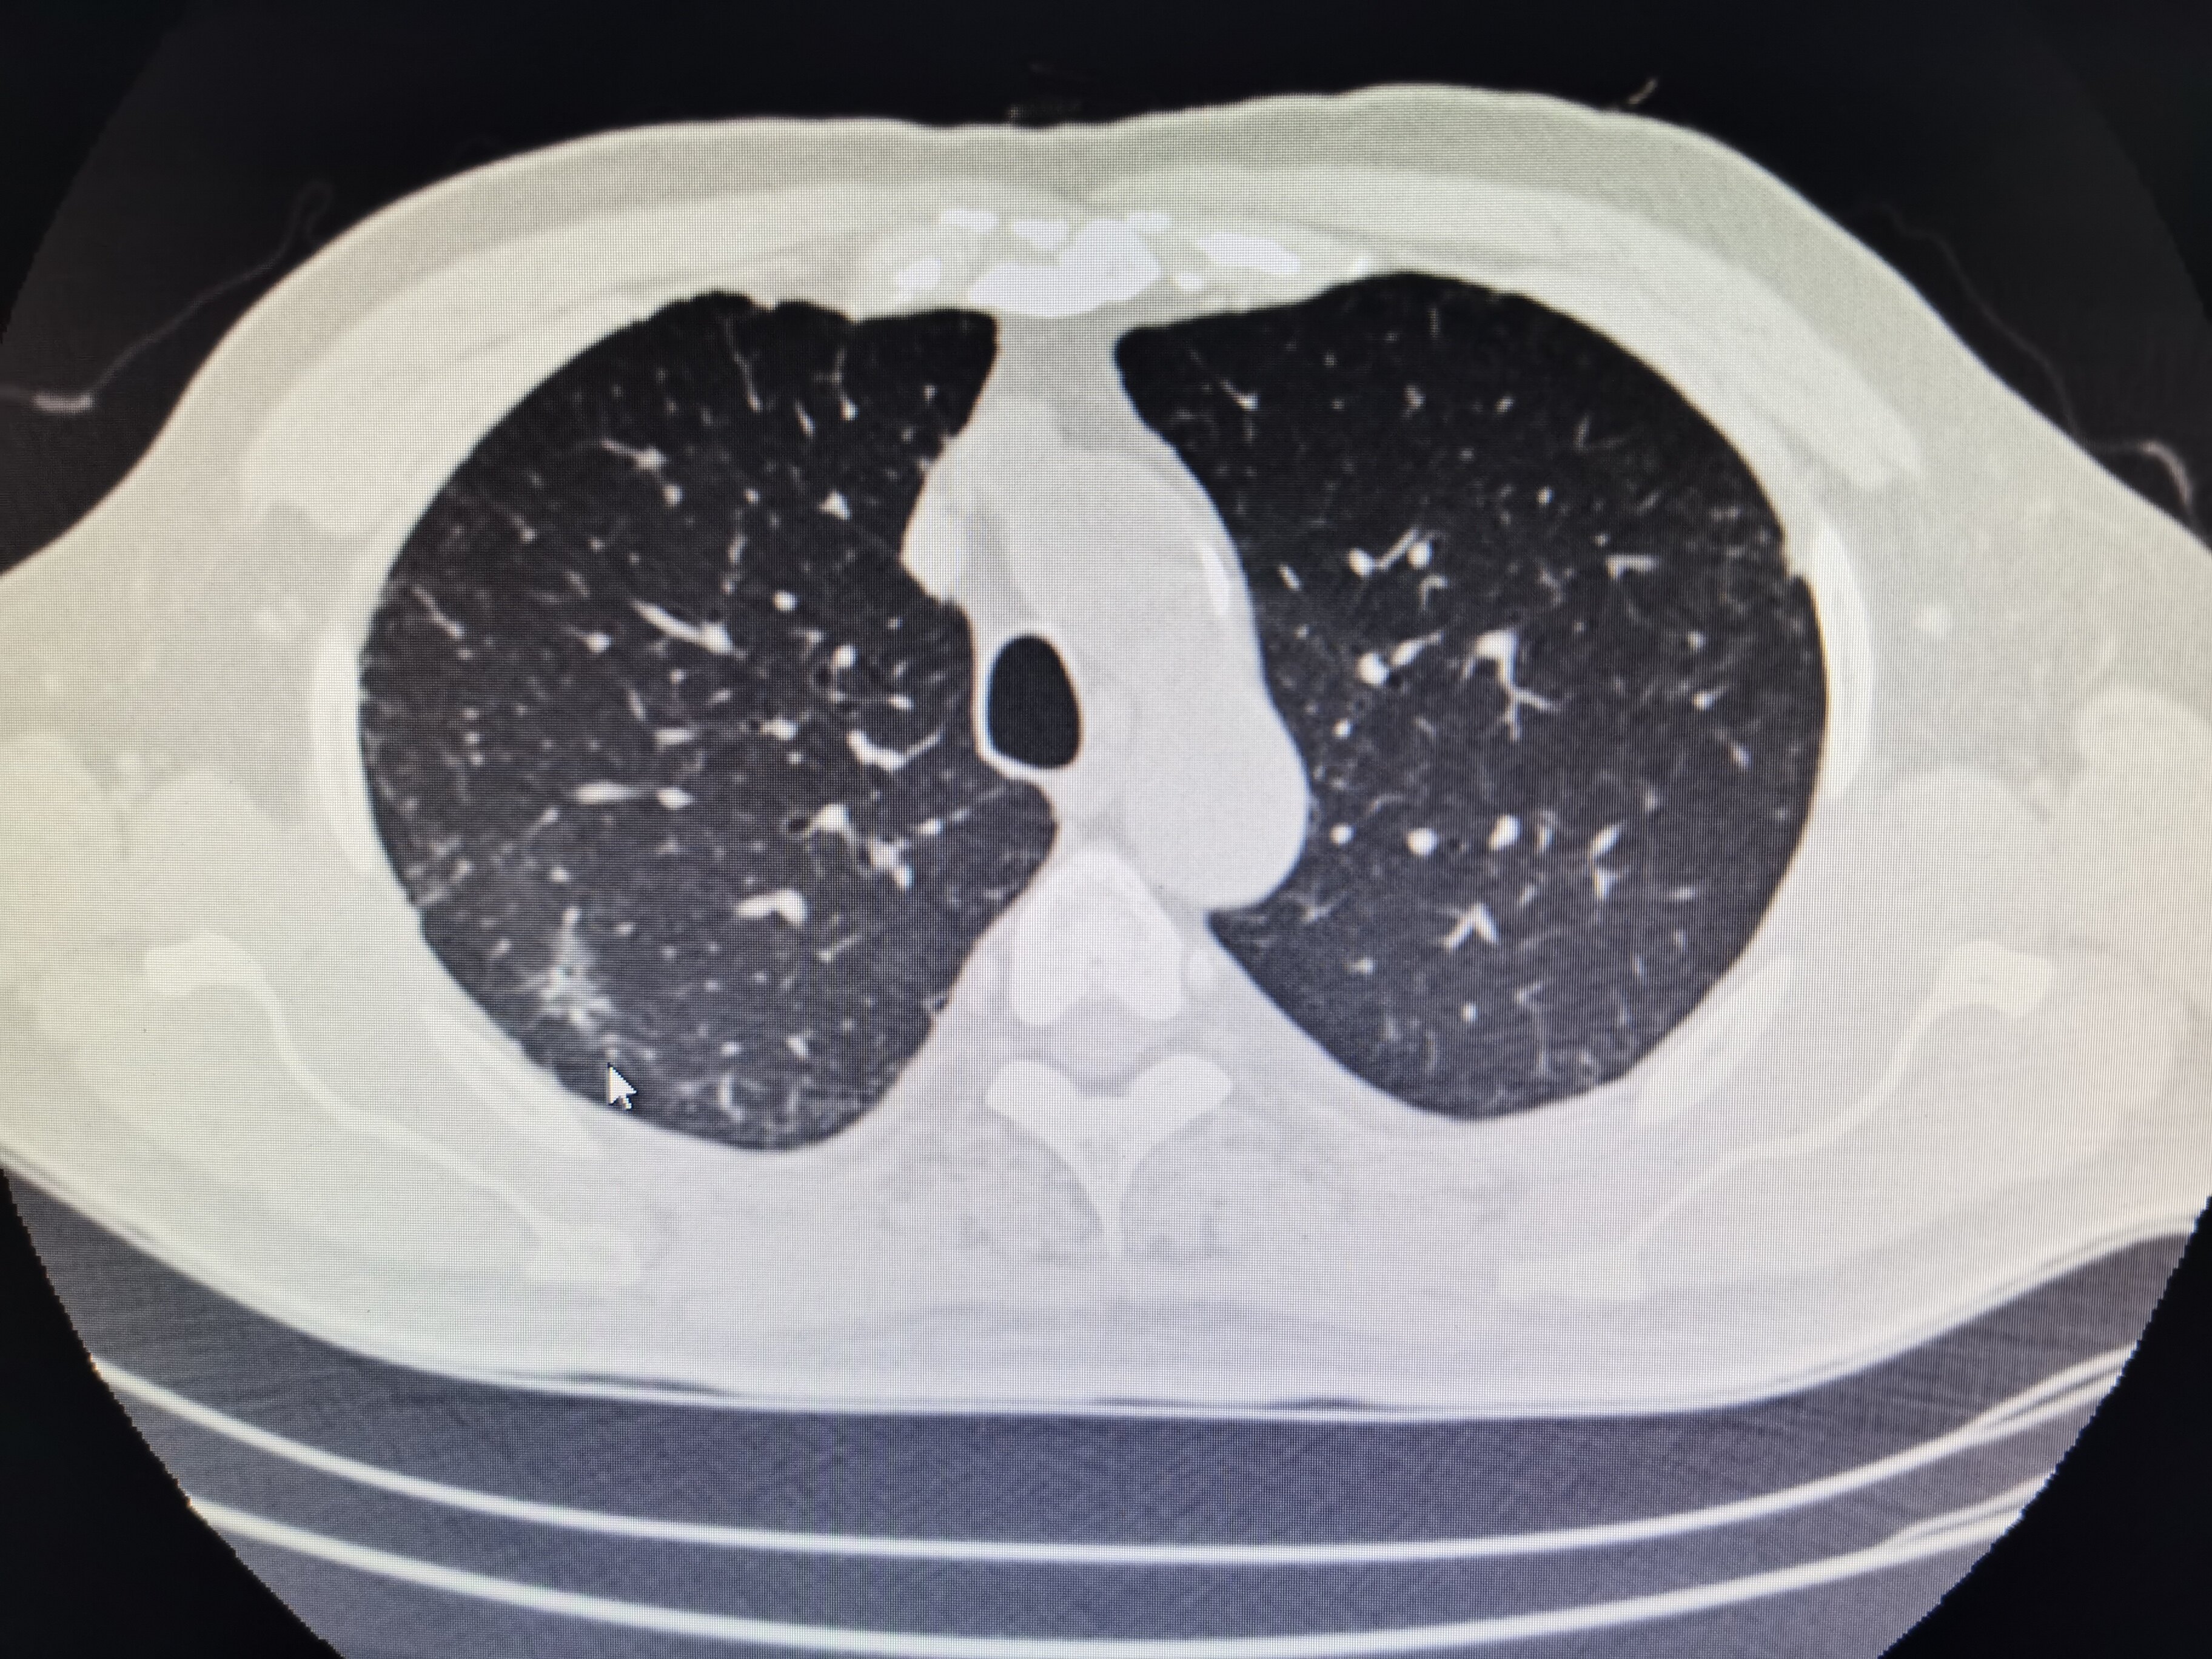

肺部结节什么原因引起的?有哪些症状?

肺部结节有哪些显性症状?

喘息、久咳、咳血、呼吸急促、声音嘶哑、发烧,尤其是与肺炎有关时、体重减轻,疲劳。届时,患者需要立即就医,才能得到准确的病情诊断和正确的干预方向。